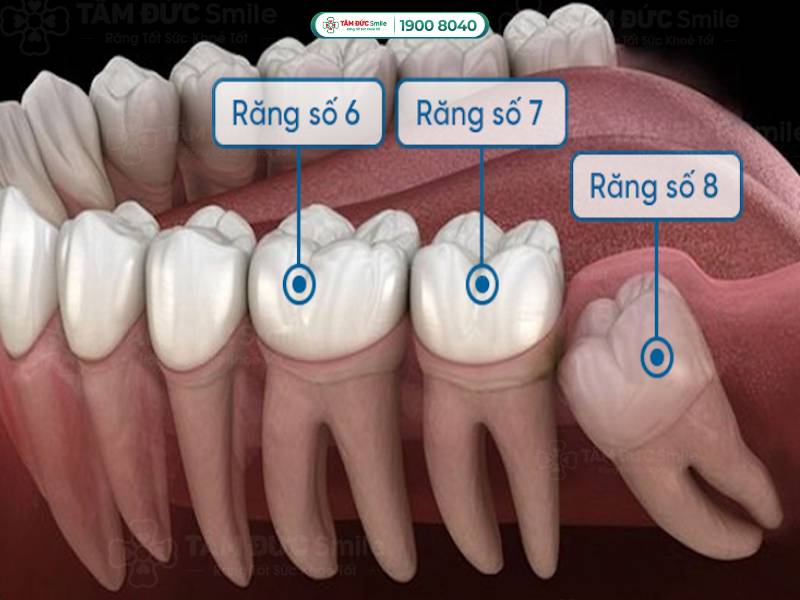

Răng số 7 nằm ở vị trí trong cùng của hàm, mọc trong độ tuổi từ 12-13 khi trẻ đã thay hết răng sữa. Nhiệm vụ quan trọng của răng số 7 là nhai và nghiền thức ăn, tạo thành một hệ thống nhai hoàn chỉnh. Vì kích thước lớn nên cấu tạo của chiếc răng này rất phức tạp, có 2-3 chân răng và nhiều rãnh trên bề mặt.

Tuy nhiên, vì nằm ở vị trí khuất và có cấu tạo phức tạp, răng số 7 dễ mắc các bệnh lý về răng miệng. Mọi người khó vệ sinh chiếc răng ở tận trong cùng, nếu xuất hiện lỗ sâu cũng dễ bị bỏ qua. Ngoài ra, vùng kẽ răng giữa số 7 và số 8 (răng khôn) lớn trở thành nơi lý tưởng của mảng bám, cao răng, vi khuẩn, dị vật,...

Răng số 7 và số 8 nằm ở vị trí trong cùng của hàm